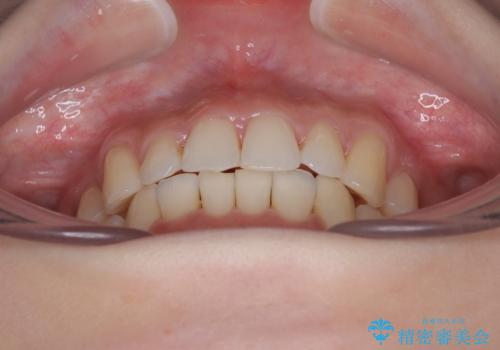

- 前歯のデコボコを気にして来院された患者様です。

全体的にデコボコが多く、特に下の前歯は隠れてしまうほどの状態でした。

左右ともに奥歯の咬み合わせが理想的な位置にあったこともあり、患者様のご希望通り、インビザラインにて矯正治療を行うこととしました。

マウスピース矯正特有の、奥歯が噛みにくくなるという現象の解消に少し期間をいただきましたが、日々の装着時間を遵守していただき、綺麗な歯列に整えることができました。